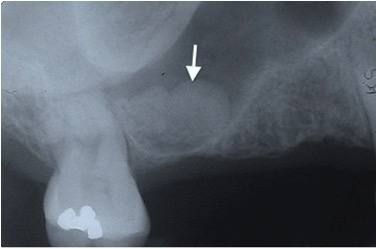

3. What condition can be seen in the following X ray?

sound radiopaque above the floor of the maxillary sinus